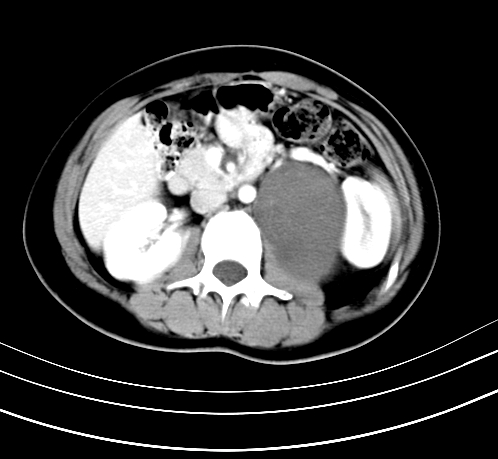

腹部平扫

动脉期